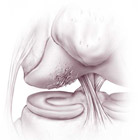

- mosaico-plastica: è una tecnica che prevede il prelievo di cilindretti di cartilagine e osso da una zona di non carico (frecce blu) del ginocchio del paziente stesso affetto da lesioni condrali focali e il loro impianto “a mosaico” nella zona di lesione (freccia rossa)

- trapianti di cartilagine: in casi selezionati per lesioni piccole e in pazienti giovani, questa procedura può dare benefici a lungo termine. Nei casi di trapianto autologo, viene prelevata dal paziente una piccola quantità di cartilagine che, inviata in laboratori altamente specializzati, viene messa in coltura; i condrociti (cellule che compongono la cartilagine articolare) opportunamente trattati, si replicano formando una neo-cartilagine che verrà successivamente impiantata nel paziente.